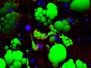

In the intricate microcosm of our bodies, different diseases may interact with each other. For example, researchers are exploring links between serous ovarian cancer (SEOC), the most common form of ovarian tumour, and the herpes simplex virus. Herpes infects over 65% of the world’s population, so is likely to occur in most SEOC patients. It also encodes small molecules, microRNAs, which manipulate gene activity; these are found in the ovaries of SEOC patients at higher levels than in healthy individuals. Each column here shows a section of cancerous tissue, with cell nuclei in blue, the tumour in yellow and surrounding connective tissues in green. In the last two columns, the merged images in the top row reveal the presence of microRNAs (in pink) in the tumour. Specific types of microRNAs are associated with more or less severe cancers, suggesting that further research into their function could help develop potential treatments.